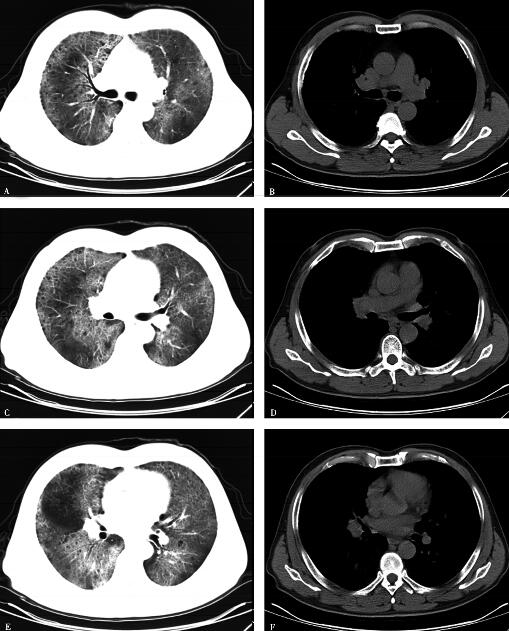

6.2010年4月20日胸部CT(图1):双肺野透光度降低,双肺弥漫分布磨玻璃影,可见支气管气象,胸膜下及双肺下叶小叶间隔增厚。

图1

胸部影像学示双肺野透光度降低,双肺弥漫分布磨玻璃影,可见支气管气象,胸膜下及双肺下叶小叶间隔增厚为主;动脉血氧分压降低,肺泡动脉氧分压差增大。同时双肺可闻及帛裂音,进一步支持初步诊断“间质性肺疾病”。结合患者长期大量吸烟史,分型首先考虑为脱屑型间质性肺炎可能性大,建议行纤维支气管镜检查协助确诊,但患者及家属拒绝。末梢血白细胞计数、中性粒细胞百分比均增高,考虑存在合并细菌感染可能,感染部位首先考虑为肺部,病原学尚不清楚。血红蛋白升高与长期缺氧导致代偿性增高有关;尽管非肿瘤性间质性肺疾病由于成纤维细胞增生可导致血CEA轻度升高,但本例患者血CEA高达34.59ng/ml,故不能除外肿瘤(尤其腺癌)的可能,需要进一步完善检查并密切随诊。虽然血CEA等均增高,但影像学无肺部肿瘤依据,考虑与肺部基础病变相关,进一步除外其他部位肿瘤并密切随诊。结缔组织疾病、心脏疾病可除外。